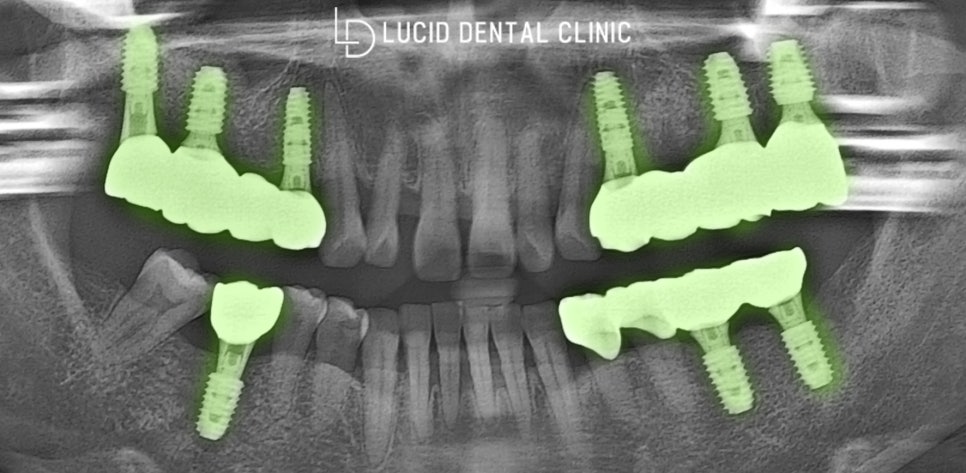

- 임플란트 수술 과정

수립한 계획을 바탕으로 치아 발치 후,

가이드 장치를 통한 식립을 마쳤습니다.

역삼동 치과 에서 제작한 임시 치아를 씌우고

회복할 때까지 잠시 대기하기로 결정했는데요

- 최종 종료 후 모습

역삼동 치과 에서 제작한 보철 체결 후,

연마 및 교합 조정으로 최종 종료했습니다.

자연치와 유사한 색조 및 형태로 제작하며

보다 높은 심미성을 추구하여 제작했는데요

환자께서도 크게

티 나지 않을 뿐만 아니라

더욱 튼튼한 기능을 얻게 되어

기쁘다고 말씀하셨어요 ㅎㅎ